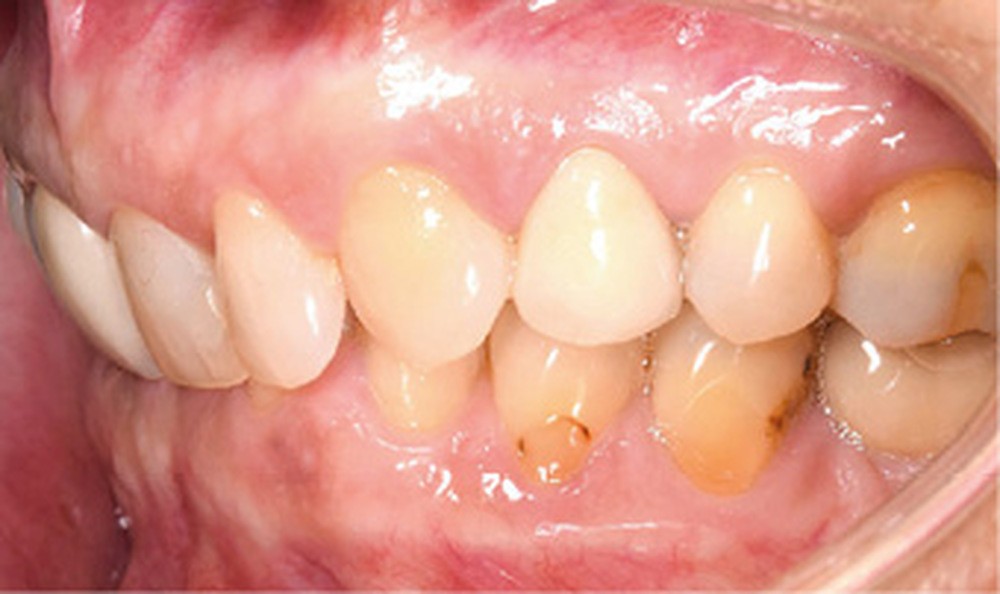

Examen endobuccal (fig. 2a-e)

L’arcade maxillaire est asymétrique et parabolique. Elle présente une mésio-position du secteur 1. On note des rotations mésio-vestibulaire de 13 et disto-vestibulaire de 23 et une palato-version incisive. Les restaurations prothétiques sur 11, 16 et 24 semblent à refaire. L’arcade mandibulaire est asymétrique et parabolique avec une couronne sur implant en 36.

Dans la dimension transversale, on constate une endoalvéolie maxillaire. Dans la dimension sagittale, on observe une classe II plus importante à droite où elle est complète de 5 mm. Le surplomb est absent et la supraclusion totale (6 mm) par supra-alvéolie mandibulaire.